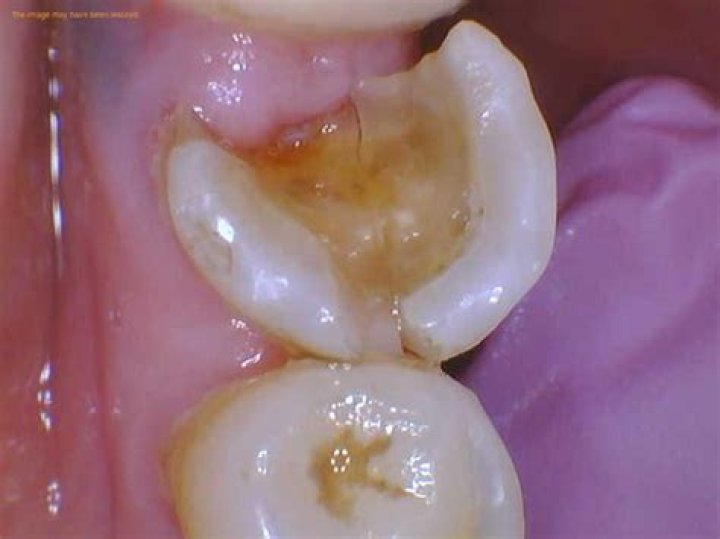

What does a rotten tooth look like?

If the process of tooth decay is allowed to continue, enamel will break down further. You may notice that a white spot on a tooth darkens to a brownish color. As enamel is weakened, small holes in your teeth called cavities, or dental caries, can form. Cavities will need to be filled by your dentist.

The possible causes of a chipped or cracked tooth include: Cavities: Cavities which can weaken the teeth and predispose you to a chipped tooth. Bad Bite: Biting down on something hard, such as an ice cube, a piece of hard candy, or a bone.